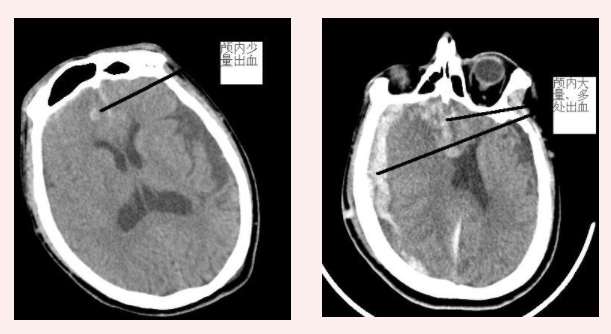

? ? ? ?患者黃先生,騎車摔倒,當(dāng)時(shí)感到輕微頭痛,在家屬陪護(hù)下到我院就診,經(jīng)CT檢查,提示顱內(nèi)少量出血,有住院指標(biāo)。但因狀態(tài)較好,黃先生未將醫(yī)生建議放心上,選擇在急診科留院觀察。10個(gè)小時(shí)后,黃先生出現(xiàn)呼之不應(yīng)、神志不清,呈昏迷狀態(tài),立即復(fù)查CT,見(jiàn)顱內(nèi)大量出血、顱內(nèi)壓高、形成腦疝,需開(kāi)顱搶救。我院神經(jīng)外科與福醫(yī)大附二院值班專家團(tuán)結(jié)協(xié)作,為黃先生緊急實(shí)施開(kāi)顱手術(shù),手術(shù)順利、搶救及時(shí),黃先生病情轉(zhuǎn)危為安,現(xiàn)已好轉(zhuǎn)出院。

傷后2小時(shí)vs傷后10小時(shí)顱內(nèi)出血量對(duì)比